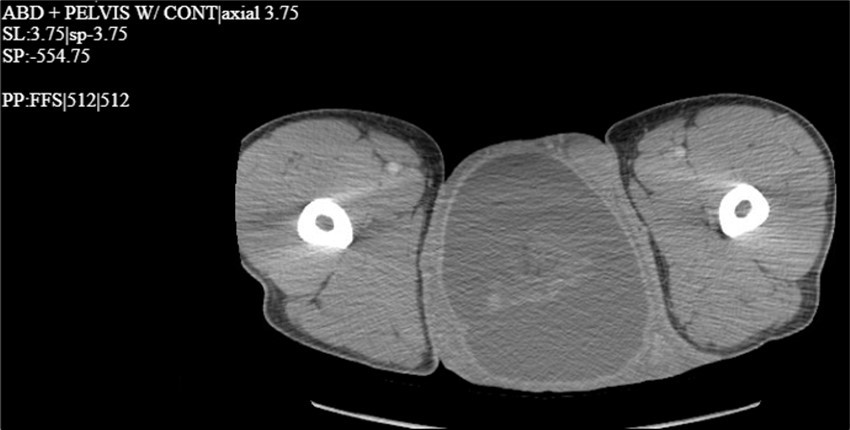

A 34-year-old male presented to the Emergency Department with complaints of large right-sided scrotal swelling, accompanied by scrotal discomfort. The patient’s past medical history was remarkable for a right-sided inguinal hernia, which had been present for several years and was repaired via right open herniorrhaphy with mesh placement three months prior. Physical examination prior to the herniorrhaphy revealed a large inguinoscrotal swelling, measuring 5 inches by 6 inches. During the herniorrhaphy, a very large hernia sac was encountered that could not be fully dissected from the cord structures and required placement of two large meshes; however, the testicles were successfully reduced back into the scrotum. Ultrasound of the right testicle revealed a large hypoechoic space with a complex collection and posterior displacement of the testicle, indicating a possible hydrocele (Figure 1, Figure 2, Figure 3, Figure 4). The patient was taken to the operating room for a right hydrocelectomy. During the procedure, it was noted that the penis was buried within the scrotal swelling, necessitating the placement of a Foley catheter to identify surrounding structures. Upon incision through the Dartos fascia, significant fibrotic tissue and fluid were encountered, making it difficult to maneuver around the hydrocele sac. Upon incising the hydrocele sac, a large collection of thick, dark brown fluid resembling old blood clots was immediately aspirated. Approximately 2 liters of fluid were drained from the sac. After identifying the testicle and cord structures, the proper placement of the testicle within the scrotum was verified. Due to excessive scrotal skin, a scrotoplasty was performed prior to suturing the scrotal skin and fascia (Figure 5). The postoperative hospital course was unremarkable. The patient was discharged with plans to return to the clinic for follow-up with the surgeon.

Figure 4.CT scan with contrast of the thigh region in the coronal plane with testicular swelling noted in between the thighs.